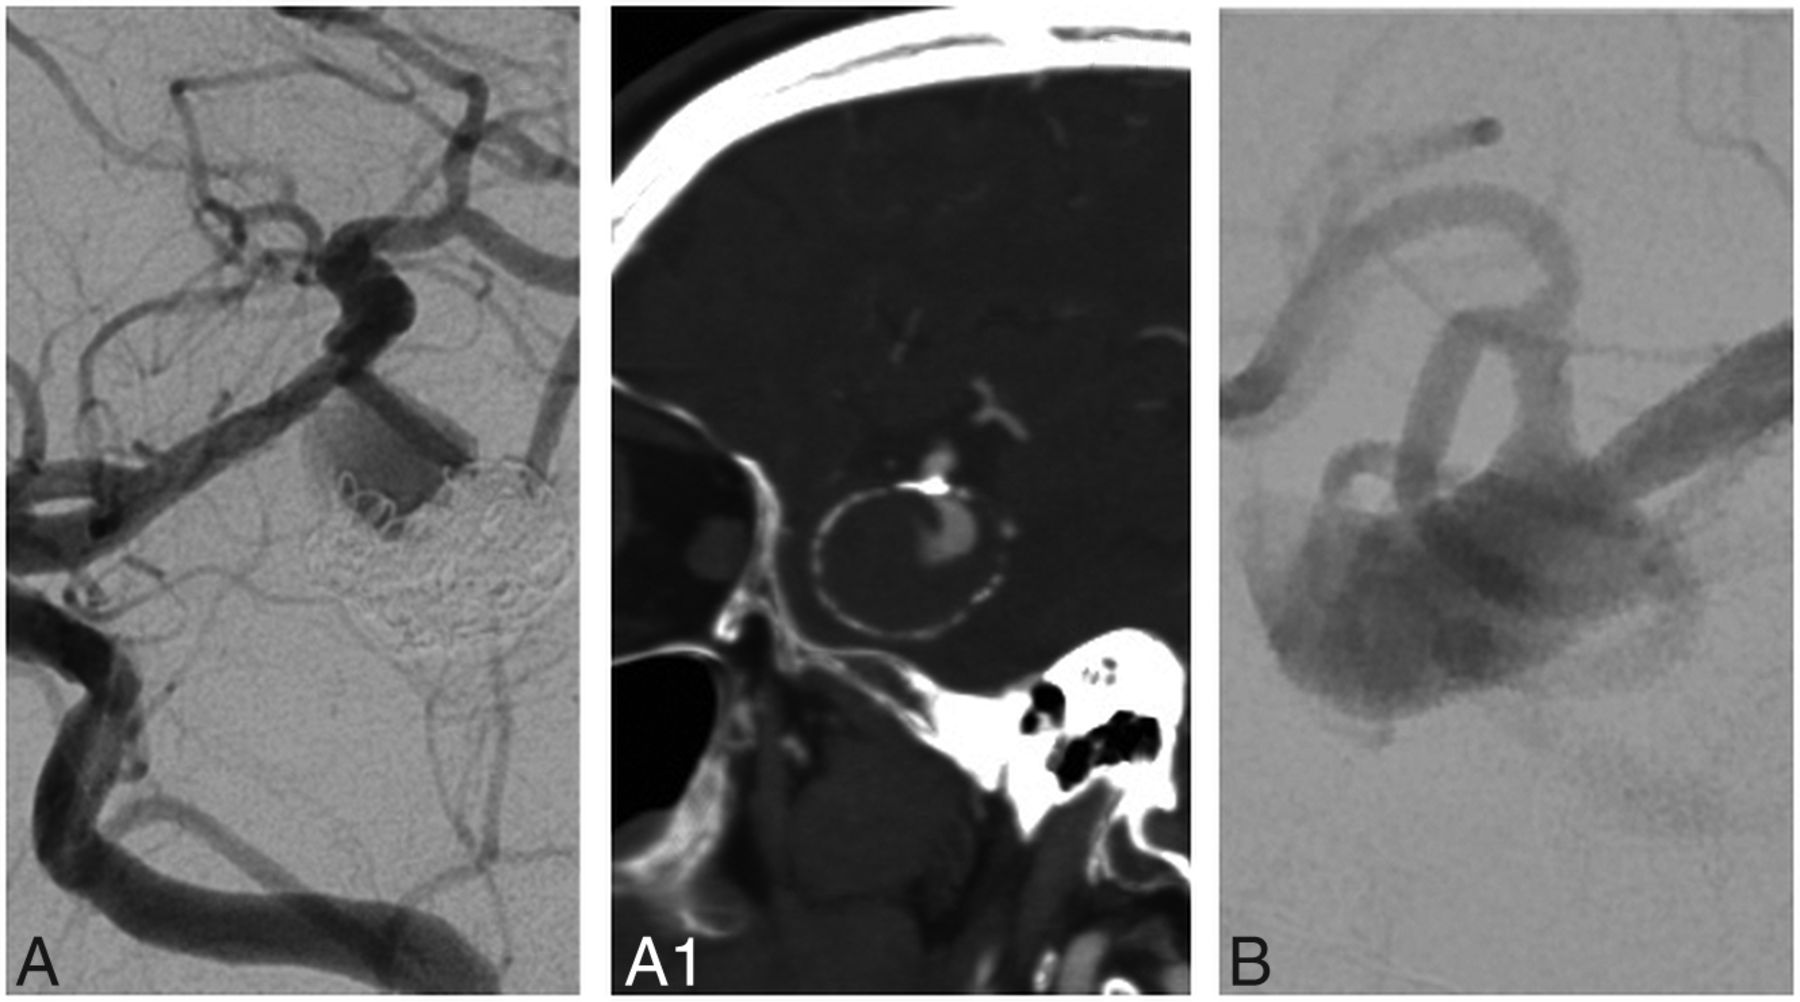

Patient and aneurysm characteristics included in the portfolio are detailed in the Online Supplemental Data, with typical cases depicted in Fig 1, and more difficult cases, in Fig 2.

Cases in which surgical management (A and A1) or endovascular treatment (EVT) (B) were rarely considered to be an option. A and A1 show a recurrent, previously coiled, calcified, partially thrombosed-but-unruptured left MCA aneurysm. Only 64% of the respondents considered surgical management an option. B, A large, wide-neck, ruptured, right MCA aneurysm. Only 39% of the respondents considered EVT to be an option for this case.